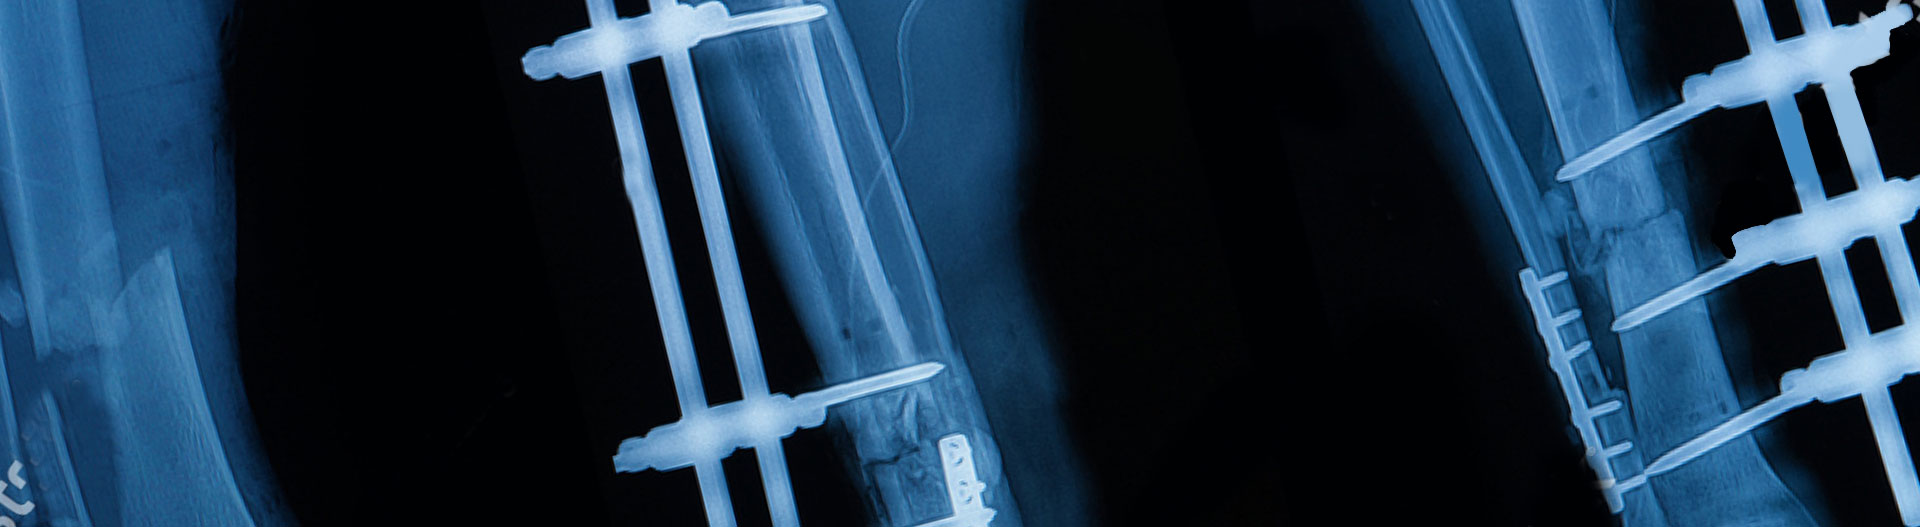

The Ilizarov Method

Extremity lengthening and reconstruction techniques are used for filling bone defects and correcting and lengthening bones with deformity...

Open and closed fractures Usually after a high energy trauma like a traffic accident or falling from a height, skin integrity is broken in addition to the fracture; this is called an open fracture.

Appropriate radical debridement necessitates excision of all necrotic bone and soft tissues, and frequently causes instability at the involved extremity. The remaining bone and soft tissue defect has to be fixed and reconstructed. The distraction osteogenesis method of Ilizarov is used successfully for achievement of union, correction of the deformity, elimination of limb length inequality and reconstruction of segmental bone defects.